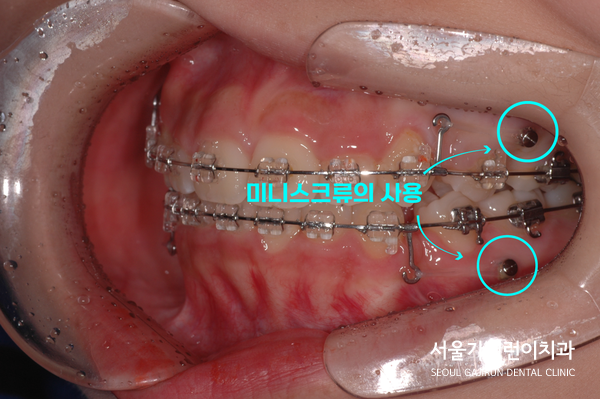

환자분의 경우 덧니 형태로 자리 잡았던 측절치를 발치를 진행했습니다. 치아이동의 공간을 확보하기 위해 상하악 제1소구치도 발치하게 되었는데요. 발치를 통한 공간은 전치의 후방이동에 사용했는데요. 초기부터 미니스크류를 이용해 충분한 힘을 주어 치아의 뿌리까지 안전하게 이동시켰습니다.

돌출입 교정에서 미니스크류는 효과적인 치료방법으로 사용되고 있는데요. 턱의 위치를 조정하거나 치아의 이동을 돕기 위해 사용되고 있습니다. 턱뼈에 직접적으로 고정된 상태로 사용되기 때문에 치아가 이동되는 동안 안정적인 힘을 제공할 수 있습니다. 이밖에도 다양한 교정장치와 함께 사용할 수 있어 개인의 상태에 맞춘 맞춤형 교정치료가 진행되는데요. 브라켓과 함께 사용해 치아의 위치를 조정할 수도 있으니 전문의와 상담해 적절한 방법을 결정하는 것이 좋겠습니다.